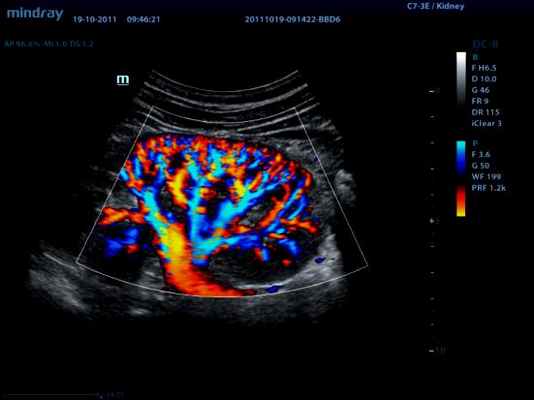

CFM (CDI, CDV, CD, CF, ЦДК и т.д.) – режим цветового допплеровского картирования по скорости

В режиме цветового допплеровского картирования по скорости (ЦДК) изображение строится также как и в B-режиме. Отличительной особенностью режима ЦДК является цветовое отображение информации о скорости и направлении движения структур в выделенной пользователем области (окно опроса). Режим ЦДК обладает ярко выраженной зависимостью от величины допплеровского угла.

Режим «энергетического» допплера является модификацией режима ЦДК и отличается от него тем, что режим ЭДК отражает движение в исследуемой области и его интенсивность, но информация о скорости и направлении при этом отсутствует. Режим ЭДК обладает практически полной независимостью от величины допплеровского угла.

Основное преимущество данного метода состоит в том, что режим ЭДК позволяет кодировать низкоскоростные потоки с значительно более высоким качеством, нежели в режиме ЦДК. Основной недостаток – большая чувствительность к любому движению, как датчика, так и исследуемой структуры.